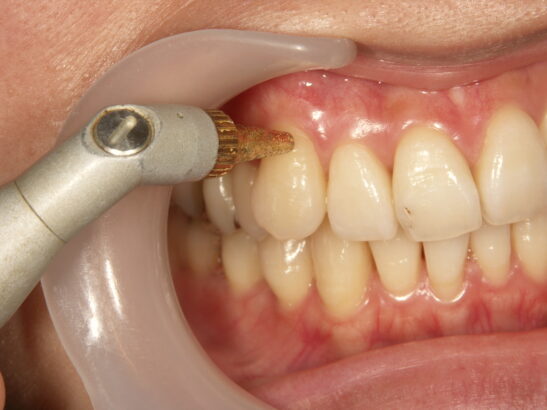

まず、歯周病などの歯周疾患が原因で知覚過敏症が起こっている場合は、当然その歯周疾患の改善の為の処置が優先されます。

歯石を除去する事によって今まで歯石に現れていた象牙質が露出し一時的に知覚過敏症の症状が強くなる場合もありますが、歯石が出ているのは細菌の塊ですので付着したままでは歯周病をかなり悪くし、どうやら知覚過敏症の症状をも悪くさせてしまう事になります。

よって、歯面及び歯根に付着している歯石は除去し、より付着しにくい環境を整えることが重要です。